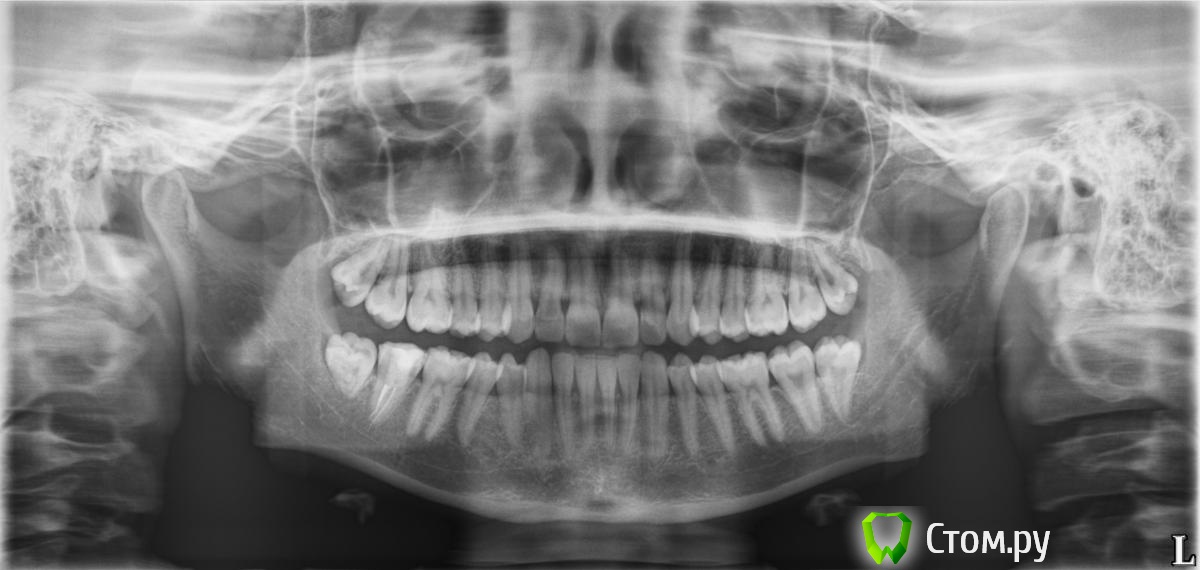

FJoe Опубликовано 23 августа, 2014 Поделиться Опубликовано 23 августа, 2014 Добрый день! Проконсультируйте, пожалуйста, по снимку.Интересует общее состояние зубов.Возможно ли сказать, на какие стоит обратить внимание в ближайшее время? Большое спасибо! Ссылка на комментарий

red_butler Опубликовано 23 августа, 2014 Поделиться Опубликовано 23 августа, 2014 Удаляйте все зубы мудрости и протезируйте 4.7 зуб (на нижней челюсти справа) Ссылка на комментарий

faity Опубликовано 23 августа, 2014 Поделиться Опубликовано 23 августа, 2014 я бы ещё ортодонтию добавил. шейки зубов оголяются? Ссылка на комментарий

diesel87 Опубликовано 23 августа, 2014 Поделиться Опубликовано 23 августа, 2014 И прицельный 26 Ссылка на комментарий

faity Опубликовано 23 августа, 2014 Поделиться Опубликовано 23 августа, 2014 и понеслась)))тогда уж и 4.7 профоткать, подозрение на выведение Ссылка на комментарий

faity Опубликовано 25 сентября, 2014 Поделиться Опубликовано 25 сентября, 2014 2.5,2.6 лечить, 4.7 наблюдать Ссылка на комментарий